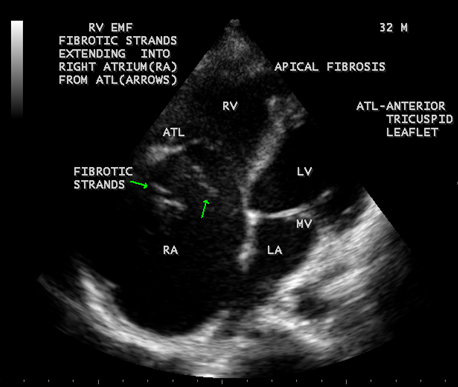

Figure 35: Endomyocardial fibrosis showing thick fibrous strands in the right atrium in a 32 -year old male and a dilated right atrium

Figure 36: Endomyocardial fibrosis showing SEC (spontaneous echo contrast or smoke) in the right atrium in a 32 -year old male.

When the endocardium is replaced by collagenous fibrosis (consist of collagen deposition and fibroblast proliferation), the final fibrotic stage is reached after several years of disease activity. Fibrotic obliteration of the apices of the affected ventricles is the hallmark of the disorder and fibrosis involving the papillary muscles and chordae tendineae leading to atrioventricular valve distortion and regurgitation. In the left ventricle, the fibrosis extends from the apex to the posterior mitral leaflet, usually sparing the anterior mitral leaflet and outflow tract and cause PML (posterior mitral leaflet) distortion and regurgitation. Like the peculiar geographical distribution, the fibrotic endomyocardial involvement stops short of the ventricular outflow tract like a ridge [17] as shown in Figures 15,29,31,35 and 44. The fibrotic tissue often creates a nidus for thrombus formation, which can be extensive. Atrial thrombi also occur and the right atrium may be aneurysmally dilated. Aneurysmal right atrium with spontaneous echo contrast was detected in a 32- year old male as shown in Figure 36 [18- Figure 3]. In addition, there are fibrosis and granular septation extending into the underlying myocardial tissue and myocyte hypertrophy is common [19]. Fibrotic process causes tethering of leaflets into ventricular walls and may mimic Ebstein’s malformation as shown in Figure 38[20],[21]. Fibrosis increases the stiffness of the heart, resulting restrictive physiology, AV (atrioventricular) valve regurgitation which has been linked to atrial arrhythmias such as atrial fibrillation as shown in Figures 19 and 20 in a 62-year old female. Atrial fibrillation has been reported in more than 30% of patients with EMF. Fibrosis impairs activation patterns of the conduction system and may provide substrate for wave breaks and reentry [22]. Fibrosis reduces conduction velocity and cause conduction abnormalities like junctional rhythms, heart blocks as shown in Figure 21 and 22 in a 75-year old female and atrioventricular conduction delay [23].

Today echocardiography is used as the screening tool at the community level as the diagnosis of EMF could be confirmed at the bedside. Echocardiography accurately assesses the pathological abnormalities of chronic disease and it is the gold standard technique for the diagnosis of EMF [36]. It reveals dense endomyocardial echocardiograms along different parts of the mural and valvular endocardium and AV valve dysfunction [37] as shown in Figures 3 to 44. The typical feature of EMF is the obliteration of trabecular portion of the ventricle and in advanced cases, there is shrinkage of the cavities creating an apical notch, regurgitation, slow flow with spontaneous echo contrast as in Figure 36 and considerable pericardial effusion. Similar to apical notch of right ventricle, a right atrial notch is well seen as contraction (or retraction) of tricuspid annulus as in Figure 40 and right atrial notch as in Figure 41 and 42, indicating the retraction of rightatrial cavity as a peculiar feature of right ventricular EMF. Biventricular enlargement as shown in Figure 40 and biatrial enlargement as in Figure 32 are the characteristic features of advanced stage of EMF. The fibrosed muscular trabeculae extending into the cavities from the walls of the chambers in the right ventricle visible as ‘cobra heads’ as in Figure 4 and in pericardial sac as in Figure 29, in the left ventricle. Aneurysmal right ventricle with scattered areas of fibrosis in the sub tricuspid region and a notch in the right atrium is well seen in a 14 –year old boy as in Figure 42 . Right atrial notch is frequently noticed in EMF patients as shown in Figure 41 in a 47- year old male with left ventricular EMF and moderate pericardial effusion.